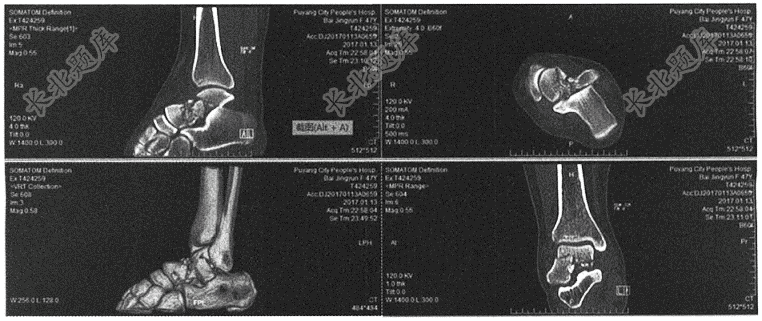

- 简答题男,45岁,高处坠落致右踝疼痛、肿胀3天为主诉。请判读下方是什么部位,什么项目检查及可能诊断